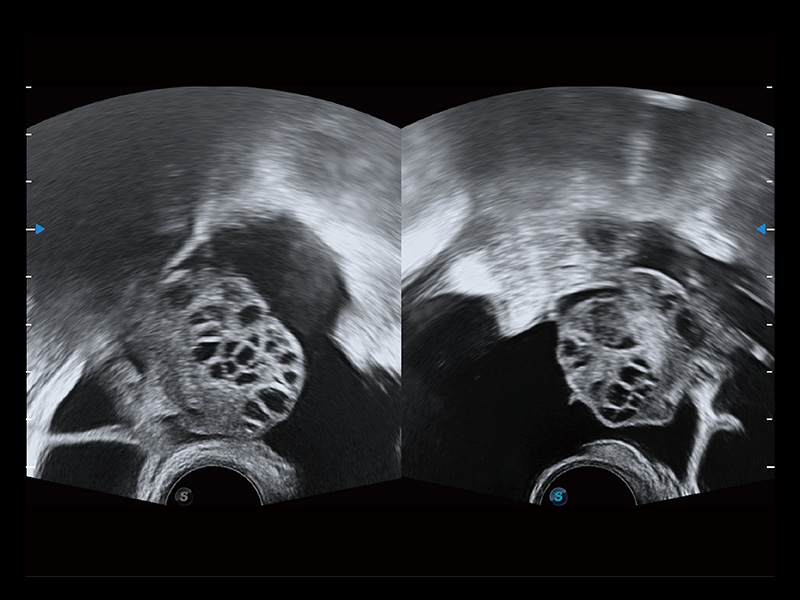

“生育问题”即关系民族复兴,也关系亿万家庭的幸福。随着婚育年龄推迟、社会压力增加等因素,越来越多人群也面临着“生不出、生不好”的问题。辅助生殖作为治疗不孕不育最有效的方法之一,也逐渐成为育儿新希望。而超声检查能为生殖需求人群的初诊评估提供宝贵的信息。 P20 Elite是狗万官方网站匠心打造的一款生殖应用型彩超。她继承狗万官方网站高端极光平台,突破性地将多款新型芯片及硬件模块进行整合,均衡了高端系统性能与小巧灵动机身。P20 Elite卓越的图像质量搭载专科探头,旨在为您提供全面的辅助生殖解决方案。

P20 Elite配备了丰富的生殖探头群和临床应用功能,在卵泡监测、穿刺取卵、胚胎移植、妊娠确认等领域,为生殖需求人群提供了新的临床机会,重新定义高端超声如何应用于生殖健康检查。

通过线上云会诊平台,实现县级医院与上级医院患者卵泡数据互联互通。避免重复性卵泡测量,提高诊断效率。